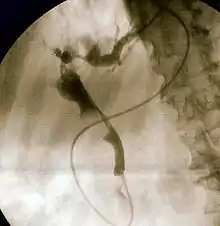

Endoscopic retrograde cholangiopancreatography (ERCP) is a technique that combines the use of endoscopy and fluoroscopy to diagnose and treat certain problems of the biliary or pancreatic ductal systems. It is primarily performed by highly skilled and specialty trained gastroenterologists. Through the endoscope, the physician can see the inside of the stomach and duodenum, and inject a contrast medium into the ducts in the biliary tree and pancreas so they can be seen on radiographs.

ERCP is used primarily to diagnose and treat conditions of the bile ducts and main pancreatic duct,[1] including gallstones, inflammatory strictures (scars), leaks (from trauma and surgery), and cancer. ERCP can be performed for diagnostic and therapeutic reasons, although the development of safer and relatively non-invasive investigations such as magnetic resonance cholangiopancreatography (MRCP) and endoscopic ultrasound has meant that ERCP is now rarely performed without therapeutic intent.[2]

The patient is sedated or anaesthetized. Then a flexible camera (endoscope) is inserted through the mouth, down the esophagus, into the stomach, through the pylorus into the duodenum where the ampulla of Vater (the union of the common bile duct and pancreatic duct) exists. The sphincter of Oddi is a muscular valve that controls the opening to the ampulla. The region can be directly visualized with the endoscopic camera while various procedures are performed. A plastic catheter or cannula is inserted through the ampulla, and radiocontrast is injected into the bile ducts and/or pancreatic duct. Fluoroscopy is used to look for blockages, or other lesions such as stones.[8][9]

When needed, the sphincters of the ampulla and bile ducts can be enlarged by a cut (sphincterotomy) with an electrified wire called a sphincterotome for access into either so that gallstones may be removed or other therapy performed.[10]

Other procedures associated with ERCP include the trawling of the common bile duct with a basket or balloon to remove gallstones and the insertion of a plastic stent to assist the drainage of bile.[11] Also, the pancreatic duct can be cannulated and stents be inserted.